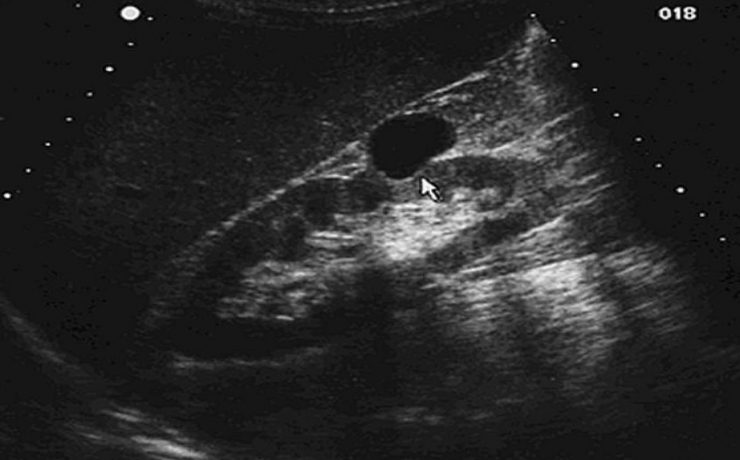

Hígado graso no alcohólico

El hígado graso no alcohólico (HGNA) es una enfermedad frecuente en nuestra práctica diaria y cada día es más tenida en cuenta, sobre todo por ser considerada la primera causa de hepatopatía crónica en el mundo occidental y por ser la elevación de las aminotransferasas el principal motivo de consulta